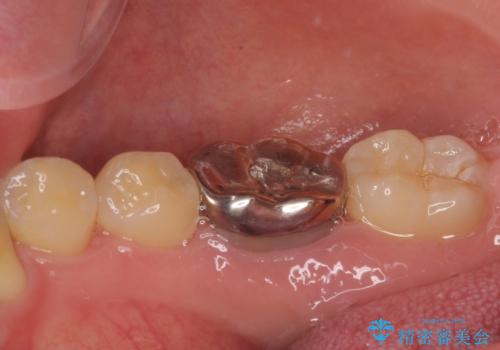

- 銀歯を白くしたいとのことで来院された患者様です。

拡大鏡視野下にて、銀歯を外して、虫歯を除去して、オールセラミッククラウンに適した形に削りました。